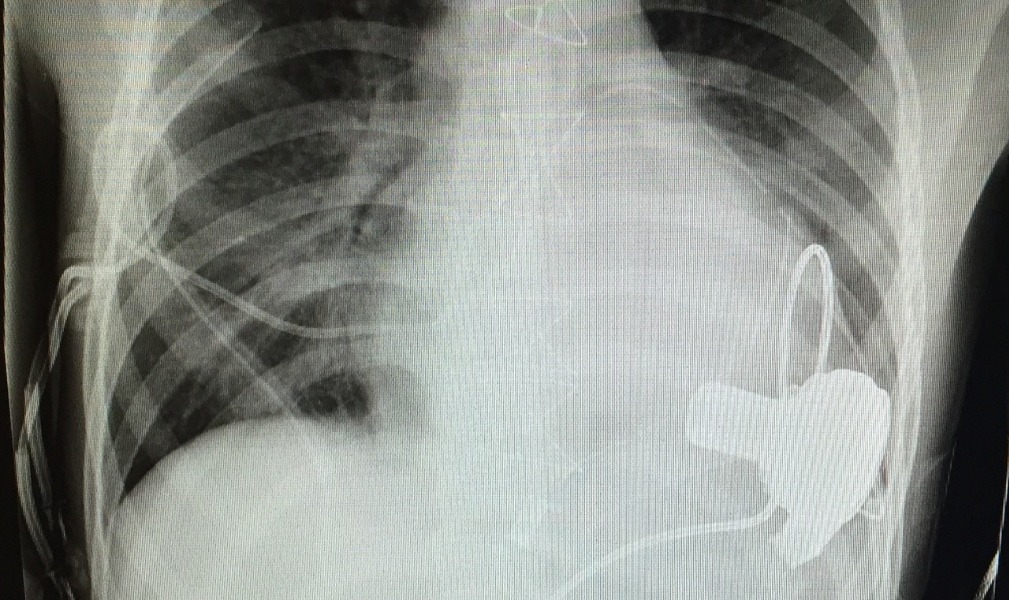

Despite several attempts to stabilise Callum on medication his heart just couldn’t cope. So on the seventh day after arrival at RCH, Callum underwent open heart surgery to have a Left Ventricular Assistance Device placed into his heart. This device along with a large number of medications will keep Callum alive until a suitable doner can be found for transplant.